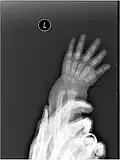

X-ray

X-ray image of right hand with thumb on left. -

Multiple fractures of the metacarpals (aka broken hand). (Right hand shown with thumb on left.) -